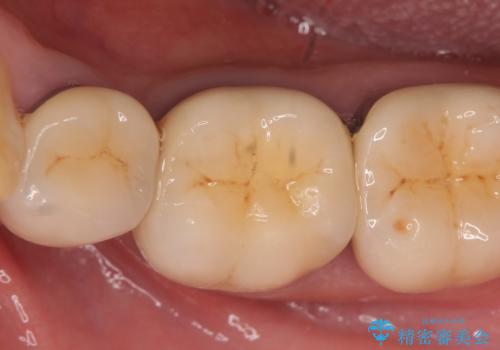

その後症状の消失を確認し、オールセラミッククラウンによる補綴を行いました。

今回用いたオールセラミッククラウンはジルコニアフレームという白い素材の上にセラミックを盛っているため、審美性が非常に高いのが特徴です。

また、ジルコニアは人工ダイヤモンドの材料にも使われているほど高い強度を持っており、そのためオールセラミッククラウンは審美性だけでなく、奥歯やブリッジの補綴も可能とするクラウンです。